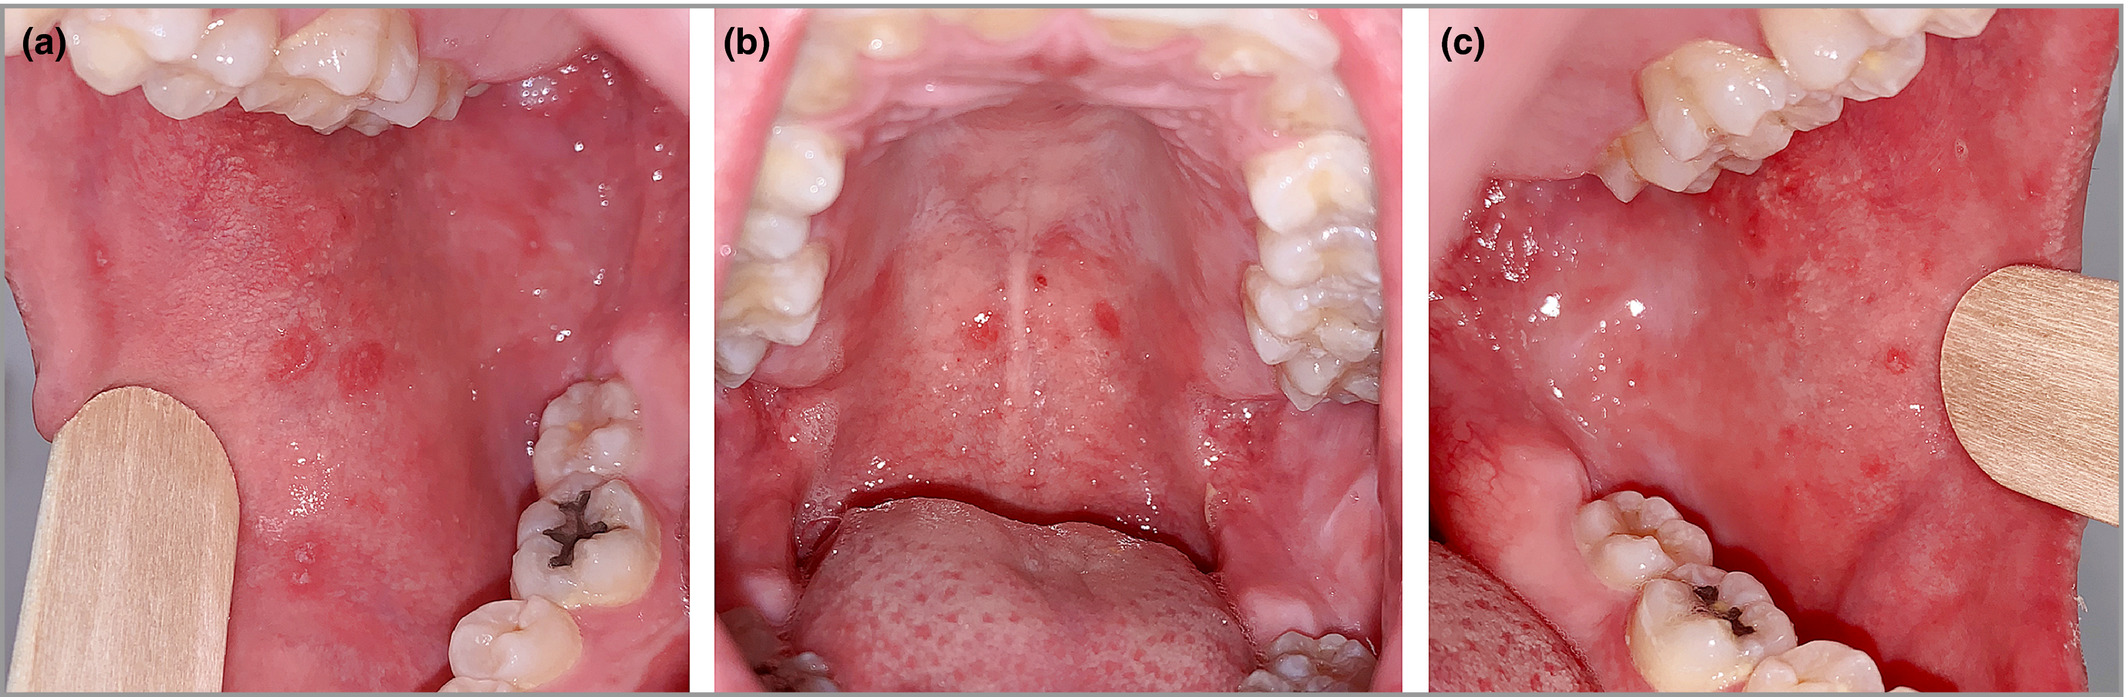

또한 이떄 특징적인입 점막의 반점, 코플릭반점(Koplik’s spot)이 나타납니다.

코플릭 반점은 구강 점막의 반점으로, 홍역에 대한 진단적 가치가 있다

코플릭반점은 피부의 발진 1~4일 전에 발생하며, 12~18시간 내에 사라집니다. (전구기 말기)

구강점막에 회백색 모래알 크기의 작은 반점이 나타납니다.